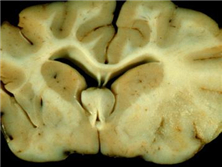

散发性脑炎伴发的精神障碍

(又名病毒性脑炎伴发的精神障碍)

目前,人们认为许多颅内感染是由病毒引起的,除了各种急性脑炎的病毒类型外,还有慢性...